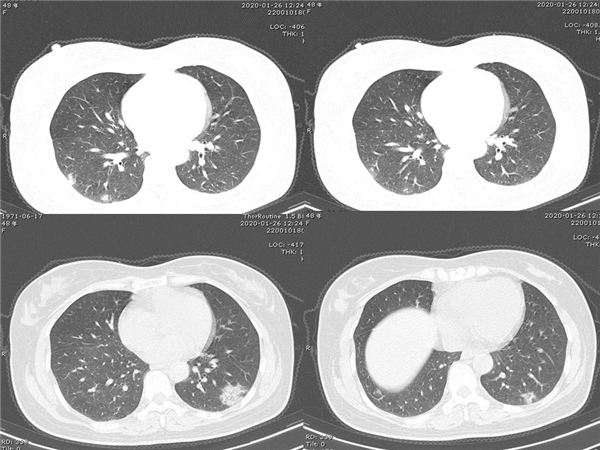

【病例分享】新型冠狀病毒感染肺部CT影像4例(常德市第一人民醫(yī)院)

幻燈片5.jpg